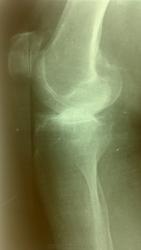

Бабушка 75 лет. Жалобы на боли в суставе. Предыдущих снимков не предоставлено. Со слов на них артроз. На снимках правого сустава Р пр-ки артроза 1 ст.

Значительное сужение суставной щели в наружнем отделе,контактный склероз. Подвывих?

Как с движениями в суставе? Артроз 3 стадии, подвывих. Возможно, боковые связки повреждены.

Коллеги, если с латеральным мыщелком бедра всё нормально,  по каким признакам артроз 3 ст. - кому авторство этого артроза присуждаете?

Может быть рассекающий остеохондрит(суставная мышь в латеральных отделах) в сочетании с гонартрозом

Мысль про асептический некроз мыщелка бедра посещала меня, но на боковой проекции совсем ровный контур обоих мыщелков, хотя и нечёткий - "мешают" межмыщелковые бугорки. Может, прямую проекцию всё-таки повторим... в должной укладке и без поворотов?)